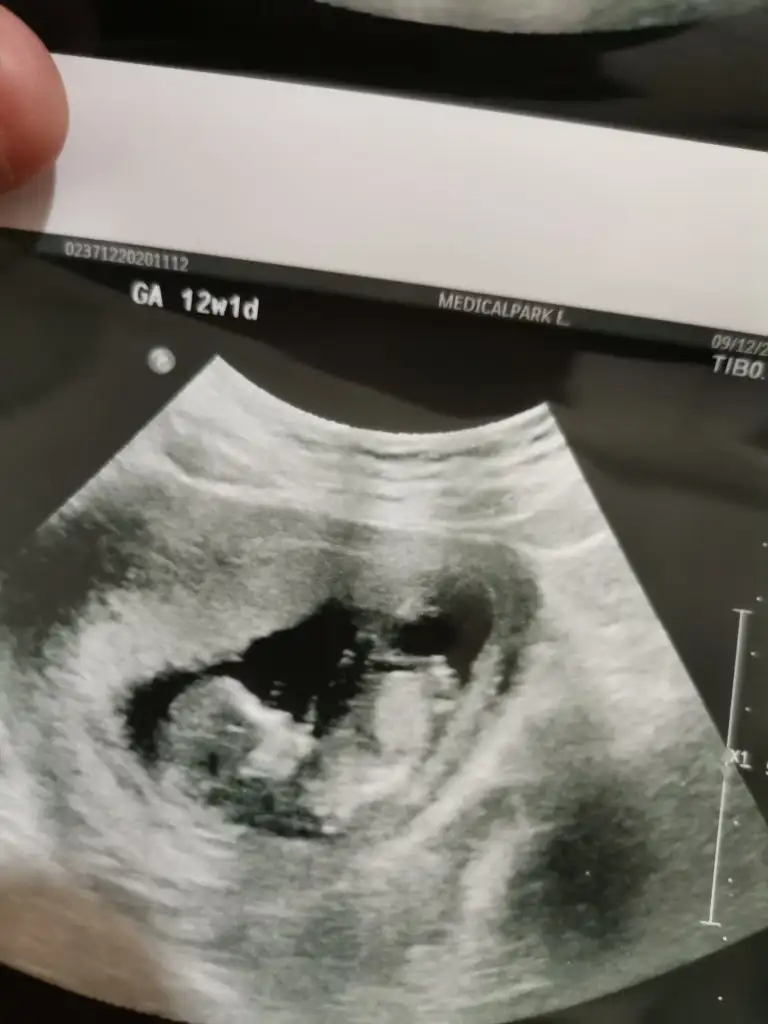

Bende 12 haftalık hamileyim cinsiyetini merak ediyorum banada bakarmısınız

Eklentiler

• IMG_20201211_144150.webp

IMG_20201211_144150.webp

17,3 KB · Görüntüleme: 60

• IMG_20201211_144131.webp

IMG_20201211_144131.webp

14,8 KB · Görüntüleme: 51